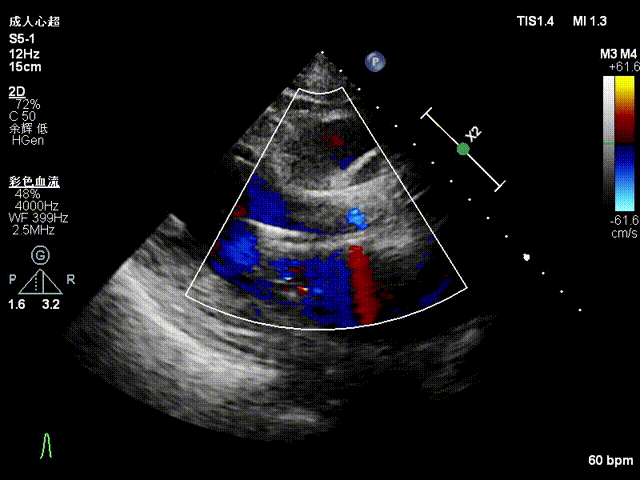

超声影像

血流动力学改善,瓣膜形态良好,无瓣周漏。